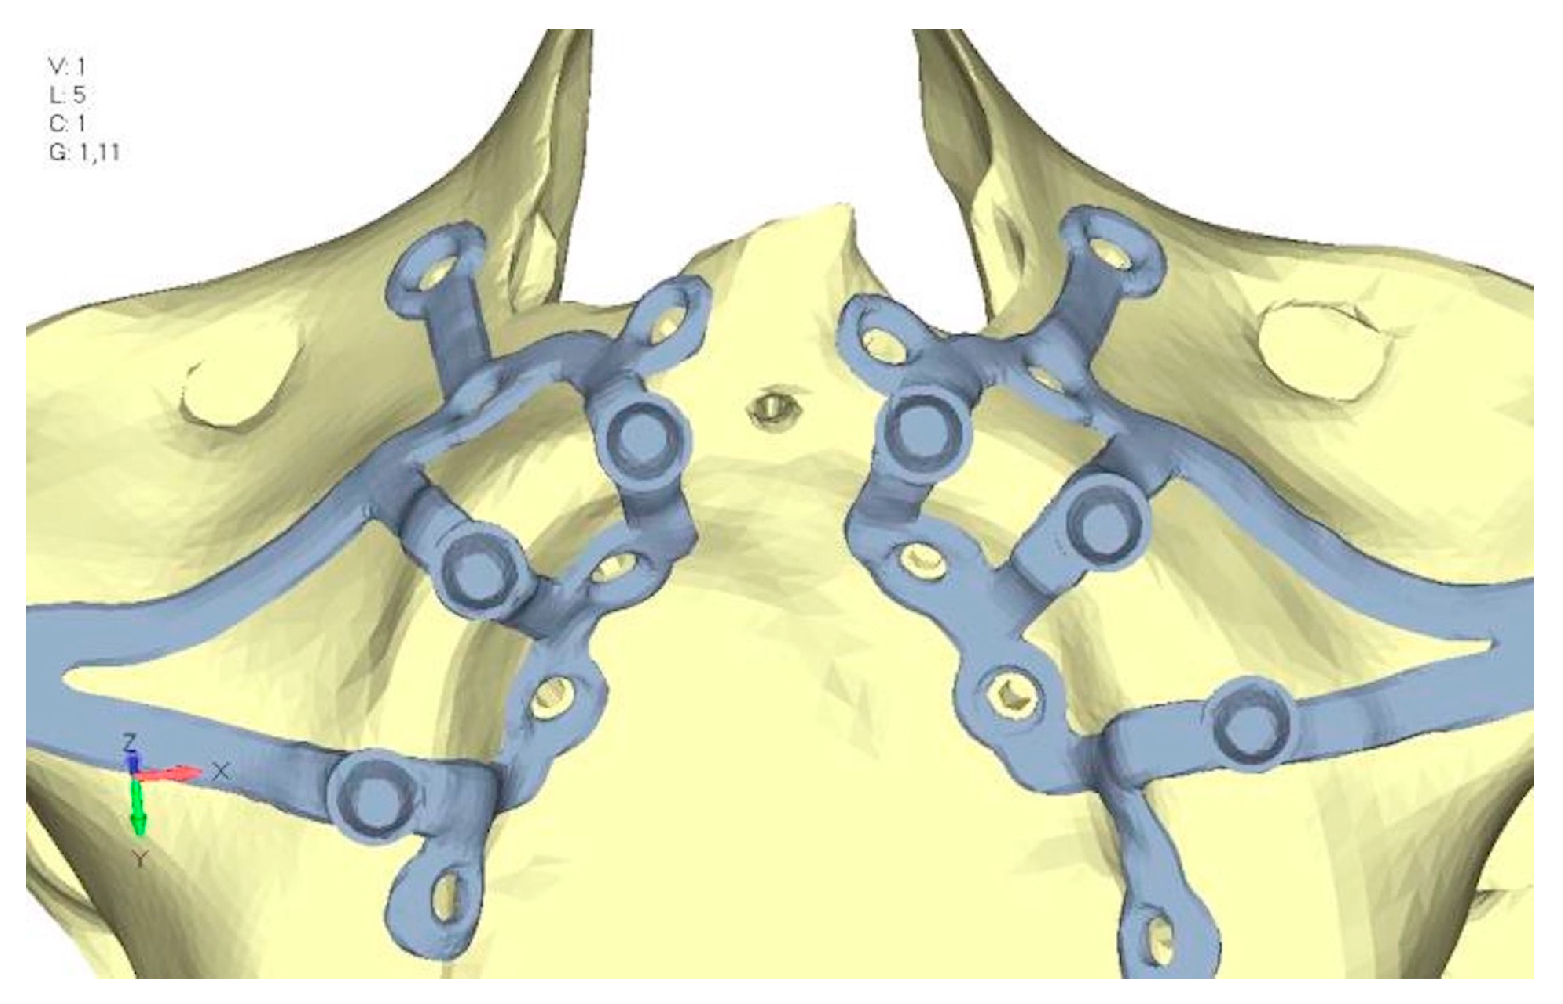

- Model V4. The previously added screw was relocated towards the frontal process, aligning it vertically with the other screws and ensuring that both arms of the first and second abutments connect to this screw (Figure 14). This solution proved to be more effective than V3; the addition of the screw reduces the stress on the other screws and on the support. The area where stress exceeds 50 MPa in the vicinity of the screws is now more contained, and the crestal support shows stresses between 30 and 35 MPa, which are absolutely acceptable (Figure 15a,b).